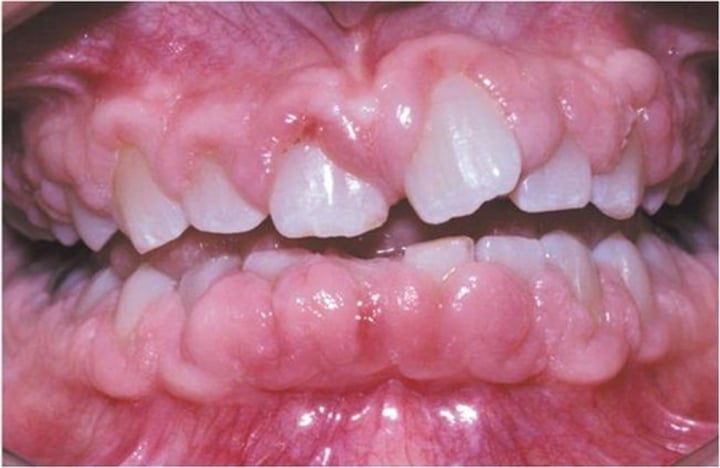

Gingival hypertrophy

Increased size of the gum encircling the teeth

<p>Increased size of the gum encircling the teeth</p>